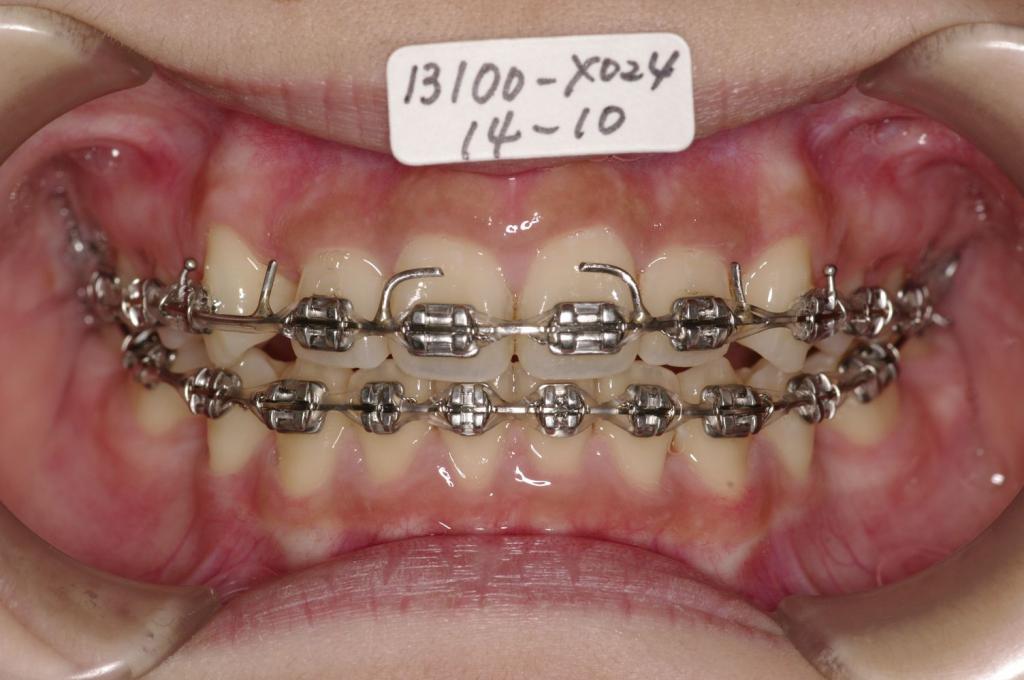

治療方法および装置:マルチブラケット装置

High pull J-hook headgear

抜歯:右上4 /左上4

右下5 /左下5

装置写真

治療前

前歯、出っ歯・開咬の矯正治療前口内写真NO.1066